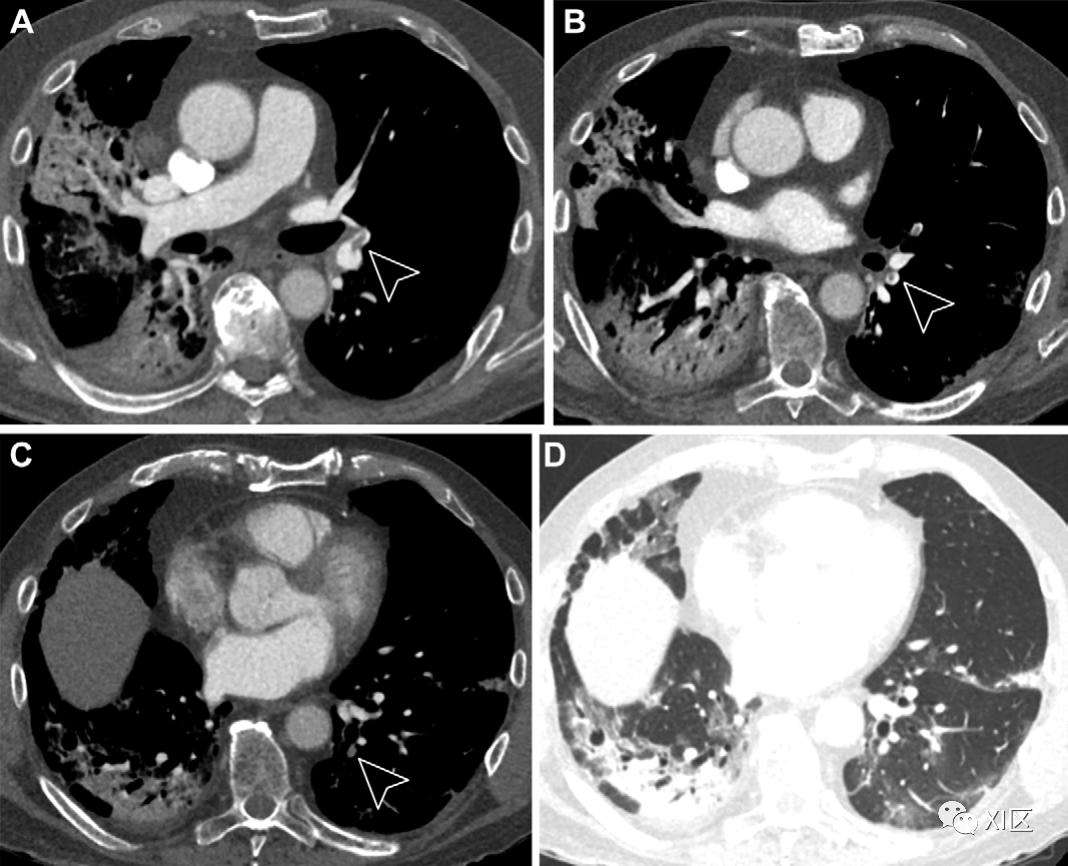

图7:一名78岁新冠肺炎患者肺血栓栓塞症的典型CT图像。(A–C)轴位增强CT图像显示左下叶远端和左上叶舌段肺动脉(箭头)存在肺血栓栓塞。(D)轴位增强肺窗CT图像显示双侧外周分布的磨玻璃样变和实变。肺血管充盈

一些研究人员一直报告称,新冠肺炎大流行早期肺血管充血,新冠肺炎患者的患病率为69%(图4)。血管充血(扩张或弯曲的形态学特征)通常在5 mm2或更大的节段和亚节段肺动脉或小动脉中观察到。充血的血管通常穿过外周GGO或围绕其周围,并被认为反映了肺泡间隔毛细血管充血,其原因是血管通透性增加,随后肺间质水肿。假设血管充血在病理上可归因于促炎因素引起的血管壁损伤和水肿,以及相应肺血管血流量增加引起的充血。这些血管变化可以反映由于微血管血栓形成导致的SARS-CoV-2受影响微血管附近的功能失调和弥漫性炎症或继发性血管扩张(即充血)引起的生理性缺氧性血管收缩的失败。在临床方面,肺血管充血的新冠肺炎患者住院和通气时间更长。